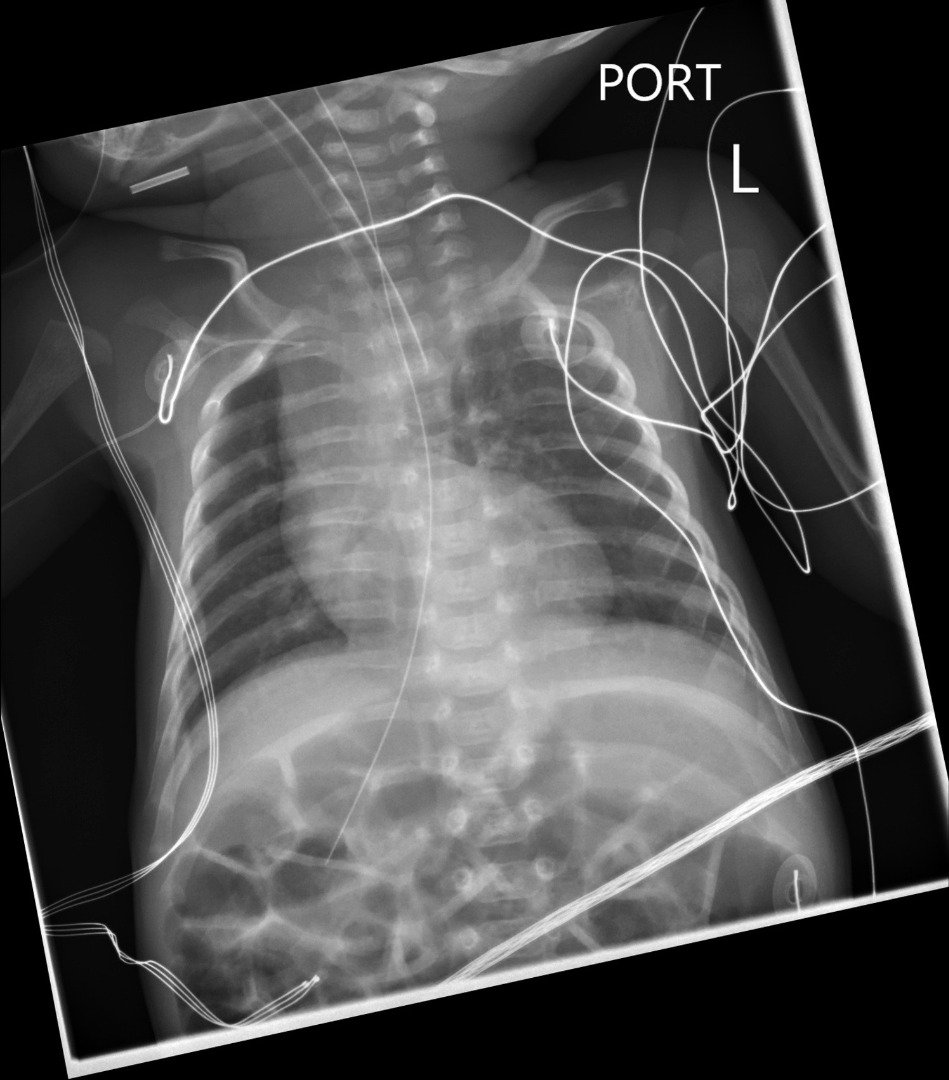

أعضاء معكوسة

بيثاني جوردان فتاة إنجليزية تعاني من حالة نادرة جدا، حيث توجد أعضاء بيثاني بطريقة معكوسة فالأعضاء التي من المفترض أن تكون في الجانب الأيمن موجودة في الجانب الأيسر والعكس صحيح، بالإضافة إلى وجود 5 نسخ من الطحال.